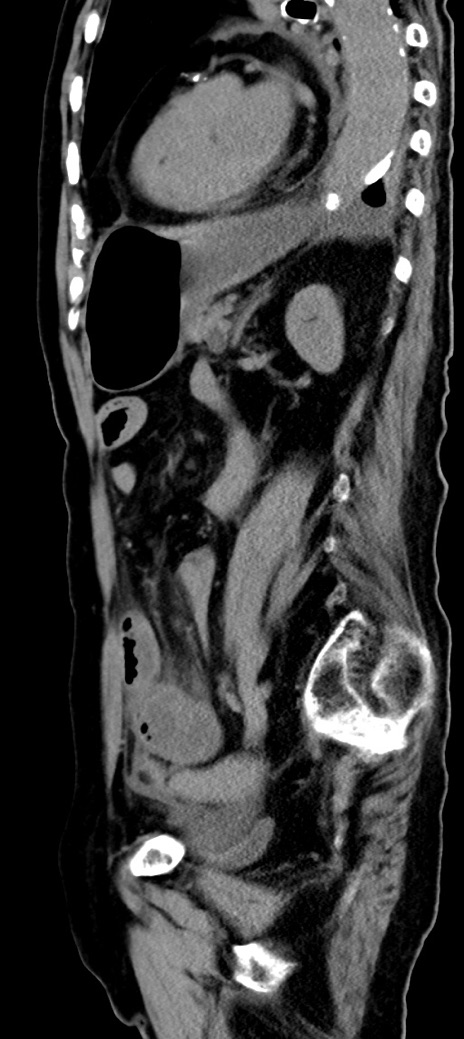

症例40(矢状断像)他院1日前

【症例】90歳代女性

【主訴】腹痛・嘔吐

【現病歴】 食欲低下、嘔吐があり昨日他院受診。肺炎と診断され入院となる。入院後より腹部全体に圧痛あり。胃管留置され経過みていたが、症状持続するため、

当院転院となる。

【既往歴】胸椎圧迫骨折、胆石症

【身体所見】腹部:中央に激痛あり、圧痛あり、反跳痛不明

【データ】WBC 17100、CRP 18.82